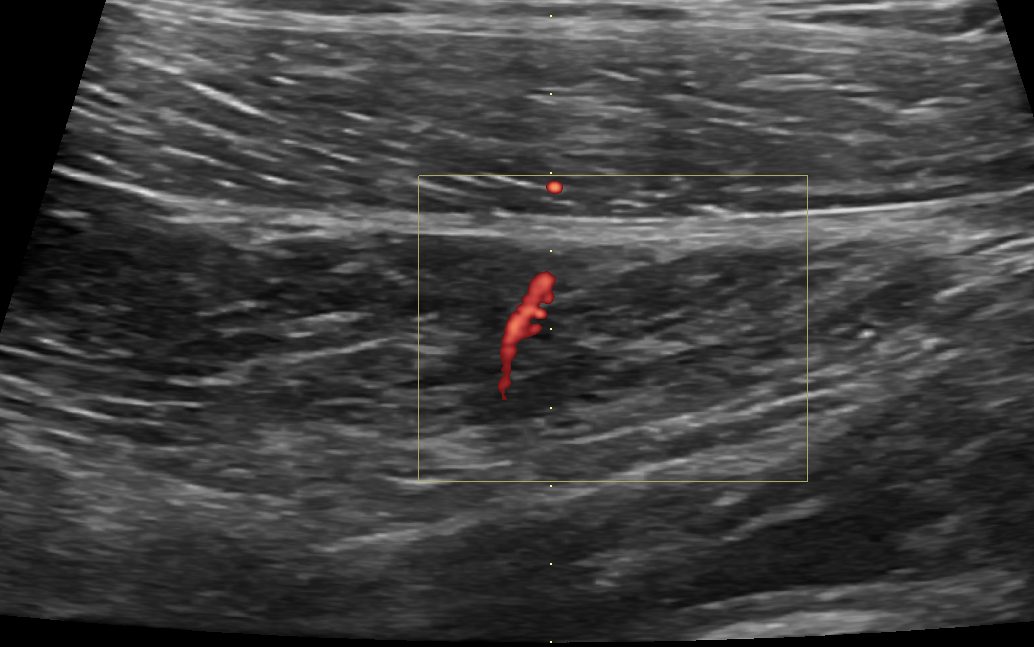

透過超音波檢查,我們可以區分出這幾條肌肉的相對位置,甚至跟對側比較,去看是否肌肉源頭(origin)、連接在骨頭處(insertion)或是肌鍵與肌肉中間的部分有撕裂或部分斷裂的狀況。

(跟對側比較,臀中肌的後側纖維比較不平整、比較腫脹且血流增加,暗示這邊有一個撕裂處)